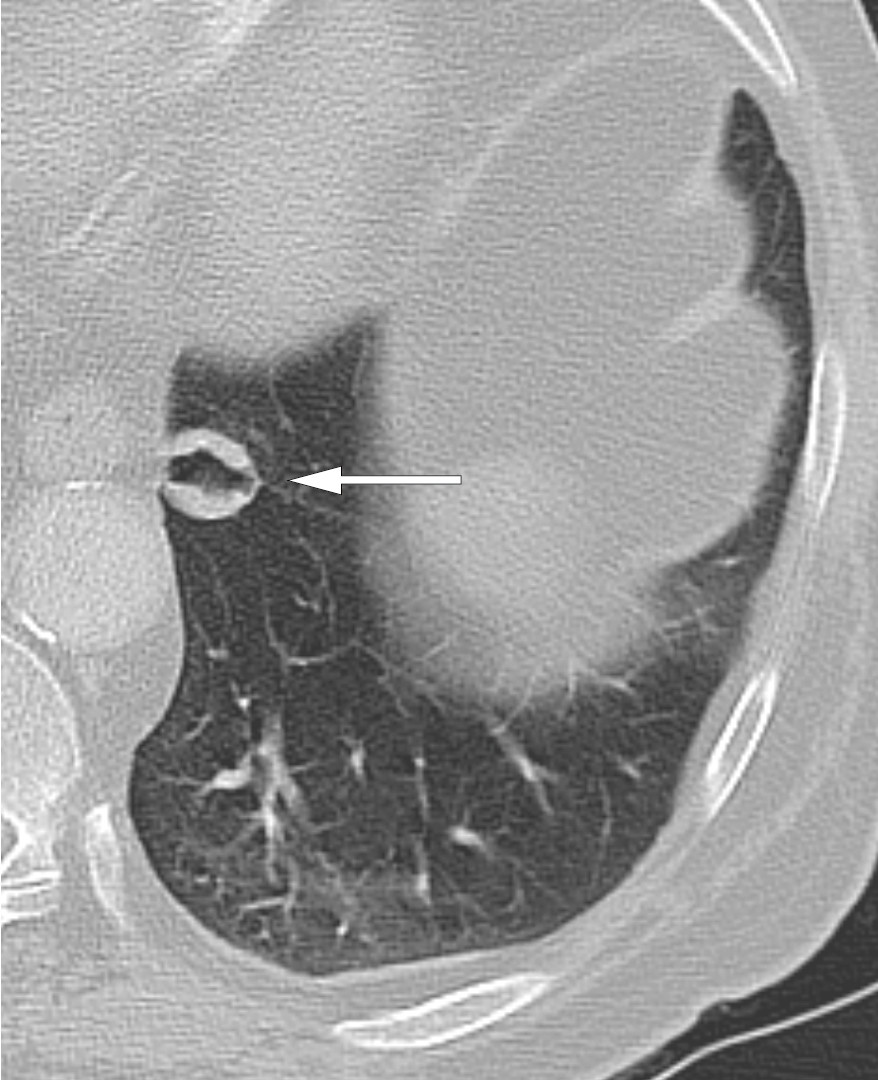

Regranskning av de to tidligere CT-undersøkelsene viste en rund kontrastladende kaviterende fortetning på 16 mm (figur 2) i venstre underlapp nær øsofagus. Transøsofageal ultralyd med finnålsaspirasjonscytologi påviste noen få grupper tettliggende celler med tydelige cellegrenser, lite cytoplasma og kjerner med lett kornet kromatin uten tydelig nukleol. Cellene ble oppfattet som lett atypiske, men av uviss opprinnelse. I tillegg inneholdt prøven regelmessige plateepitelceller og sannsynlig reaktivt sylinderepitel, antatt fra stikkanal gjennom øsofagus og lunge. Materialet var for sparsomt for immunhistokjemiske undersøkelser.

Ytterligere to år senere ble det på kontroll hos lungelege bemerket økende sentral fedme, og det ble målt kortisol kl. 14, som var 750 nmol/l. Han ble innlagt for ny endokrinologisk utredning. Her kom det frem at han det siste halvåret på nytt var blitt hoven i ansiktet, fikk lettere blåmerker og var mer urolig. Han hadde hypertensjon, 160/105 mm Hg, rundt ansikt og sentral fedme med tynne ekstremiteter. Bentetthetsmåling avdekket osteopeni med T-skår −1,9 i lårhalser. Kortisolverdiene var 437 nmol/l morgen og 529 nmol/l kveld, med korresponderende ACTH-verdier 17,4 og 16,7 pmol/l. Kveldsverdiene for kortisol i spytt var forhøyet, og kortisol ble ikke supprimert verken etter kort eller lang deksametason-suppresjonstest. Døgnurinsamlingen viste fortsatt normal mengde fritt kortisol, og MR hypofyse viste normale funn. CT avdekket cystiske forandringer i pankreas med utvidelse av pankreasgang, og tumoren i venstre lunges underlapp målte 17 mm og var blitt mer homogen. Tumor ble beskrevet å ha bred tilfesting til pleura og kunne være pleural. CT-funnet i pankreas ble vurdert til ikke å være malignitetssuspekt, og kontroll med magnetisk resonanskolangiopankreatografi (MRCP) ble planlagt seks måneder frem i tid.